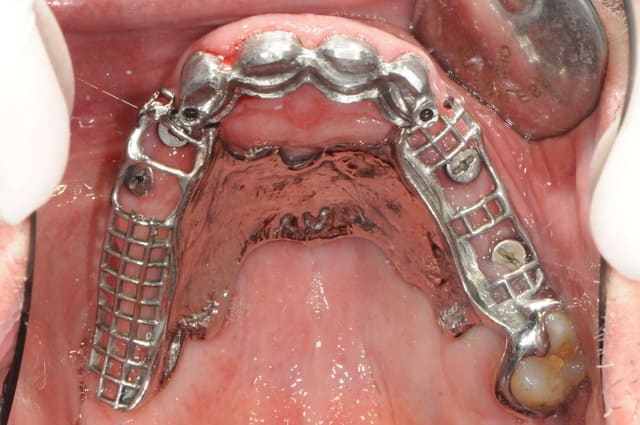

la suite c'est pose 4 implants, ceramique, stellite sur locators (beaucoup moins couteux qu'une barre et plus facile à nettoyer)

au final, c'est un patient heureux avec un stellite super stable.

Mais, juste à noter que sur le plan technique, 4 locators sur deux hemi-arcades : attention le parallélisme : trés trés délicat à gérer, au risque de se retrouver avec 3 actifs et un inutilisable.

Sur la photo "5658", il y a rougeur importante sur la

crête/gencive. Je crois que ton occlusion est trop forte. Dommage qu'il manque un appui plus postérieur dans ce coin.

mais non, c'est une photo avant juste avant la pose du nouvel appareil. ici, la gencive est un peu traumatisée par le vieux partiel résine qui servait de cache misère.

j'aurai bien voulu, mais cela aurit demandé un sinus lift (non accepté par le patient)

en fait le boulot n'est pas complétement terminé car après les implants sur 35/36 qui sont ici visibles je doit corriger la courbe occlusale en m'occupant de 43à46